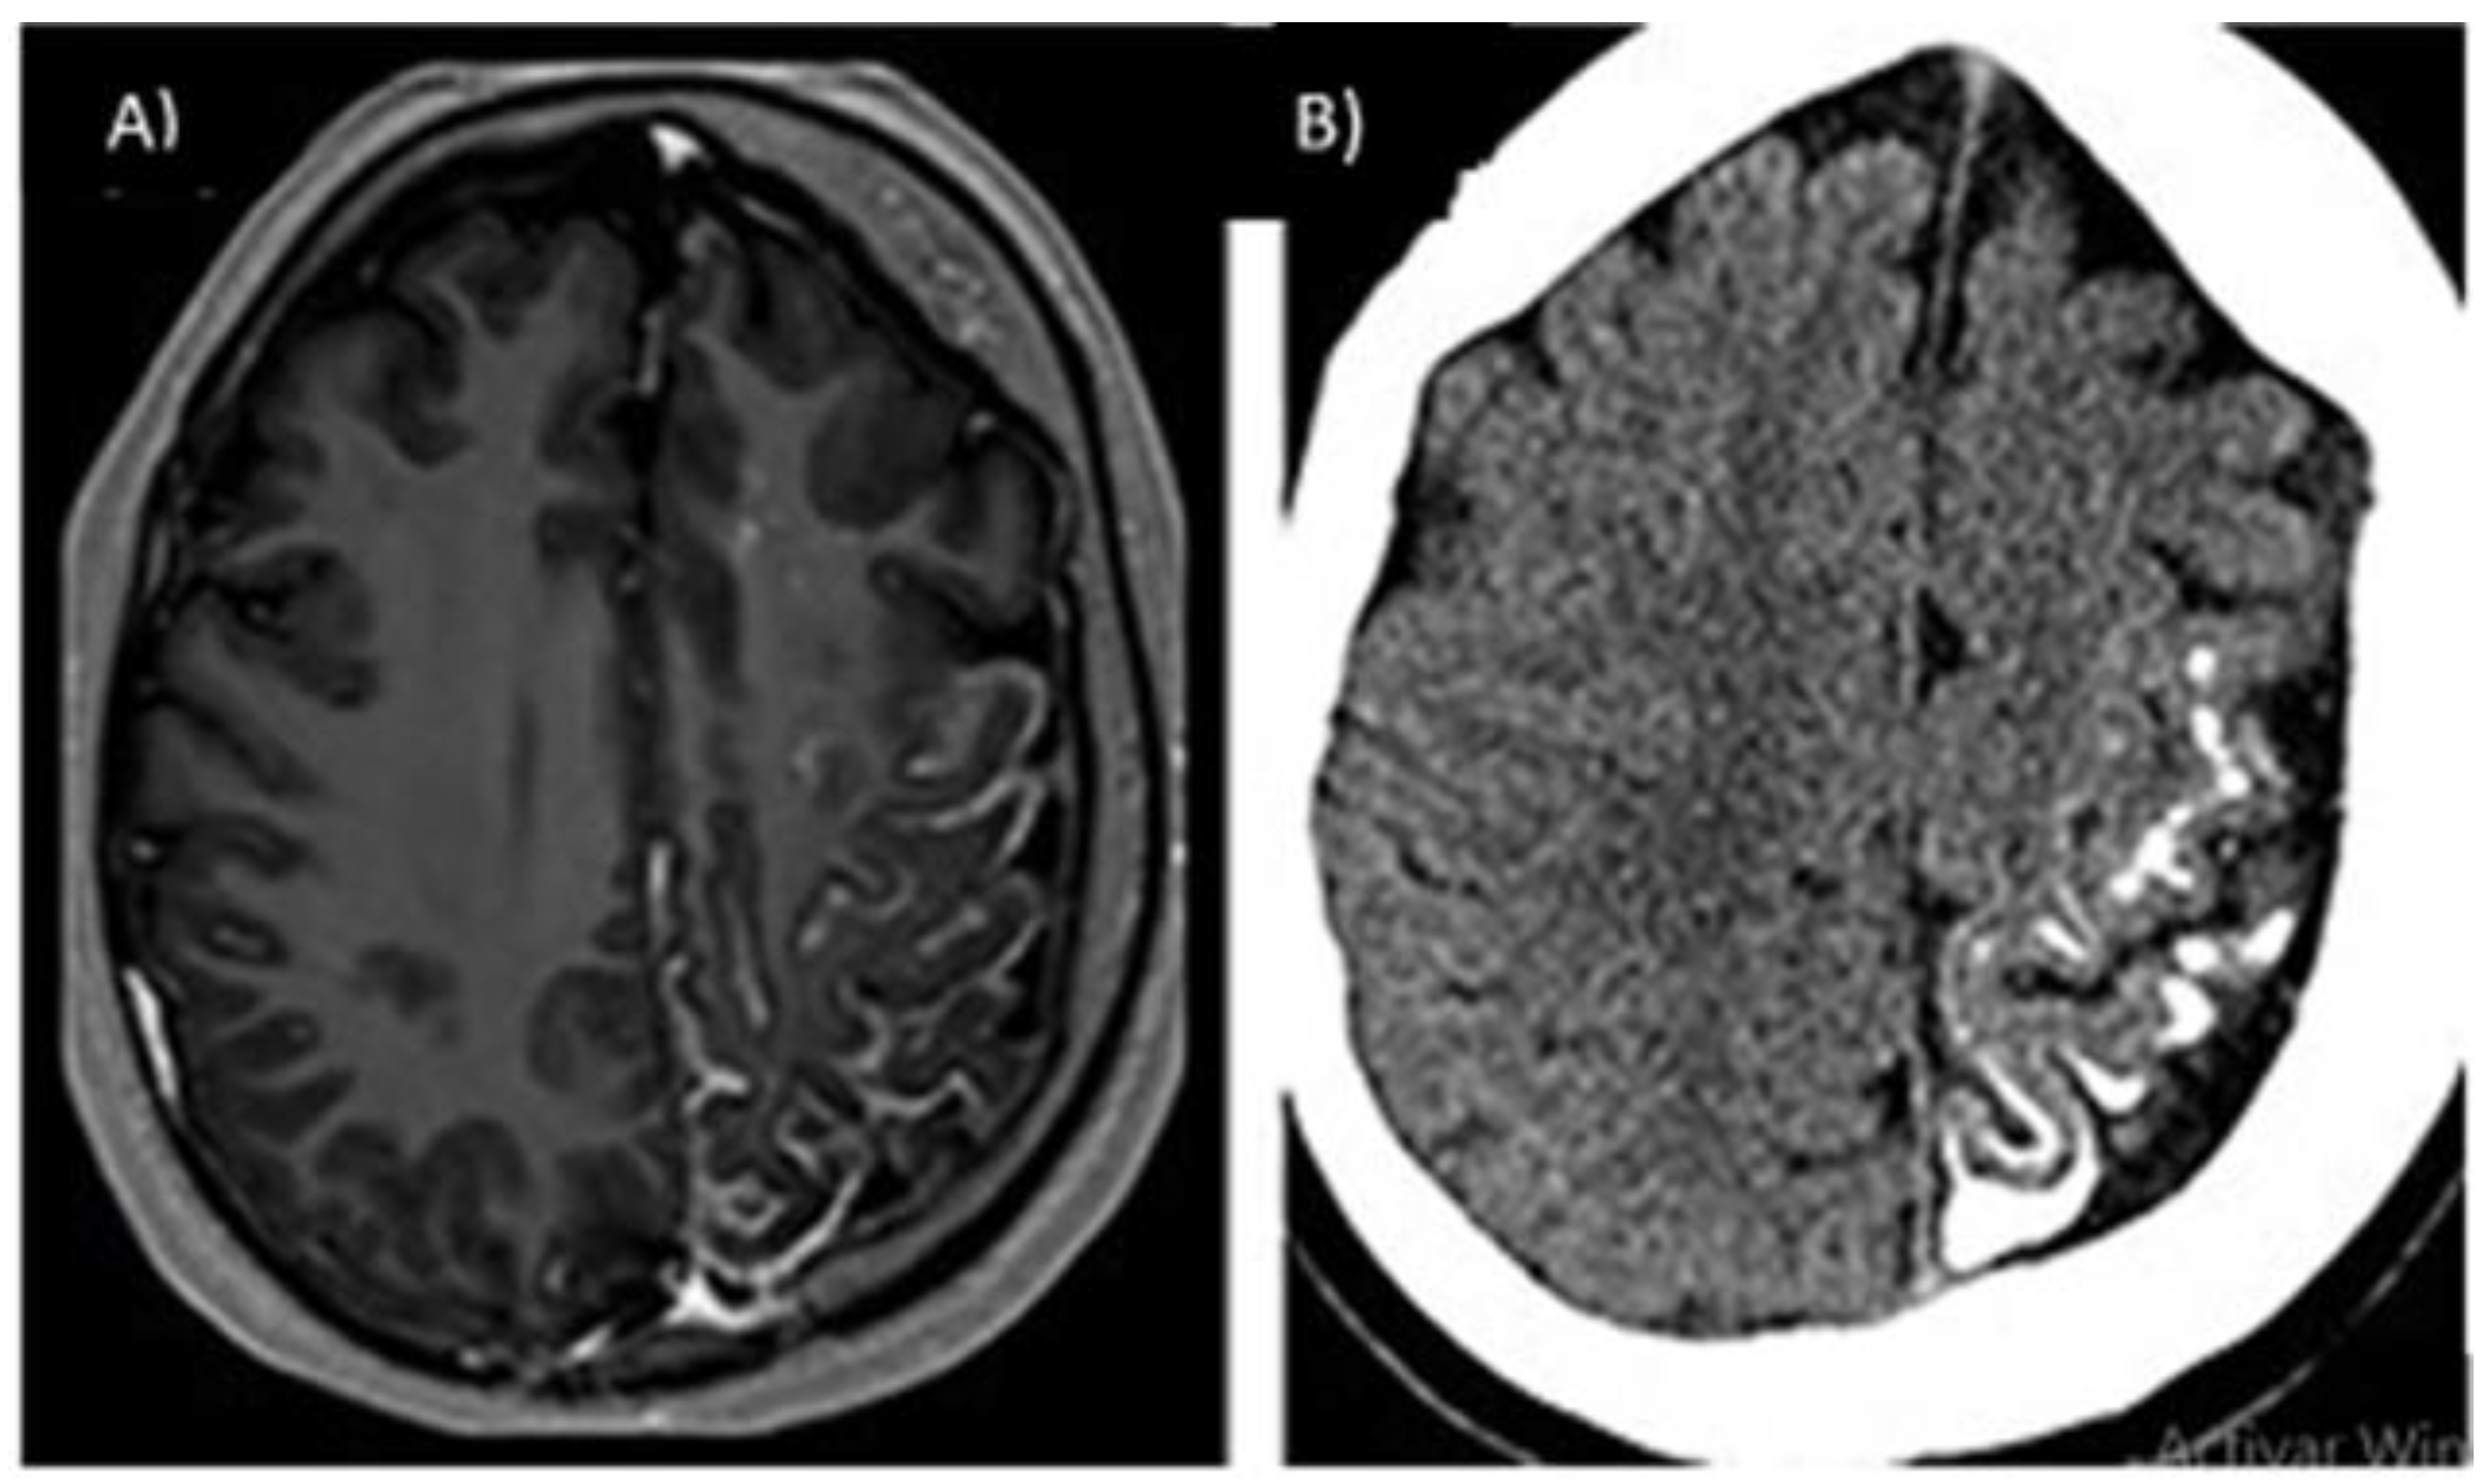

3.3.2. Capillary-Venous Angioma (Sturge–Weber)

- Bianchi, F.; Auricchio, A.M.; Battaglia, D.I.; Chieffo, D.R.P.; Massimi, L. Sturge-Weber Syndrome: An Update on the Relevant Issues for Neurosurgeons. Childs Nerv. Syst. 2020, 36, 2553–2570. [Google Scholar] [CrossRef]

- Bertani, R.; Garret, B.; Perret, C.M.; Batista, S.; Koester, S.W.; Azeredo, R.; Guimarães Cavalcante Carlos de Carvalho, T.; Almeida, J.A. Undiagnosed Sturge-Weber Syndrome as a Differential Diagnosis of Seizures and Deep Cerebral Venous System Dilation: A Case Report. Cureus 2021, 13, e19111. [Google Scholar] [CrossRef]